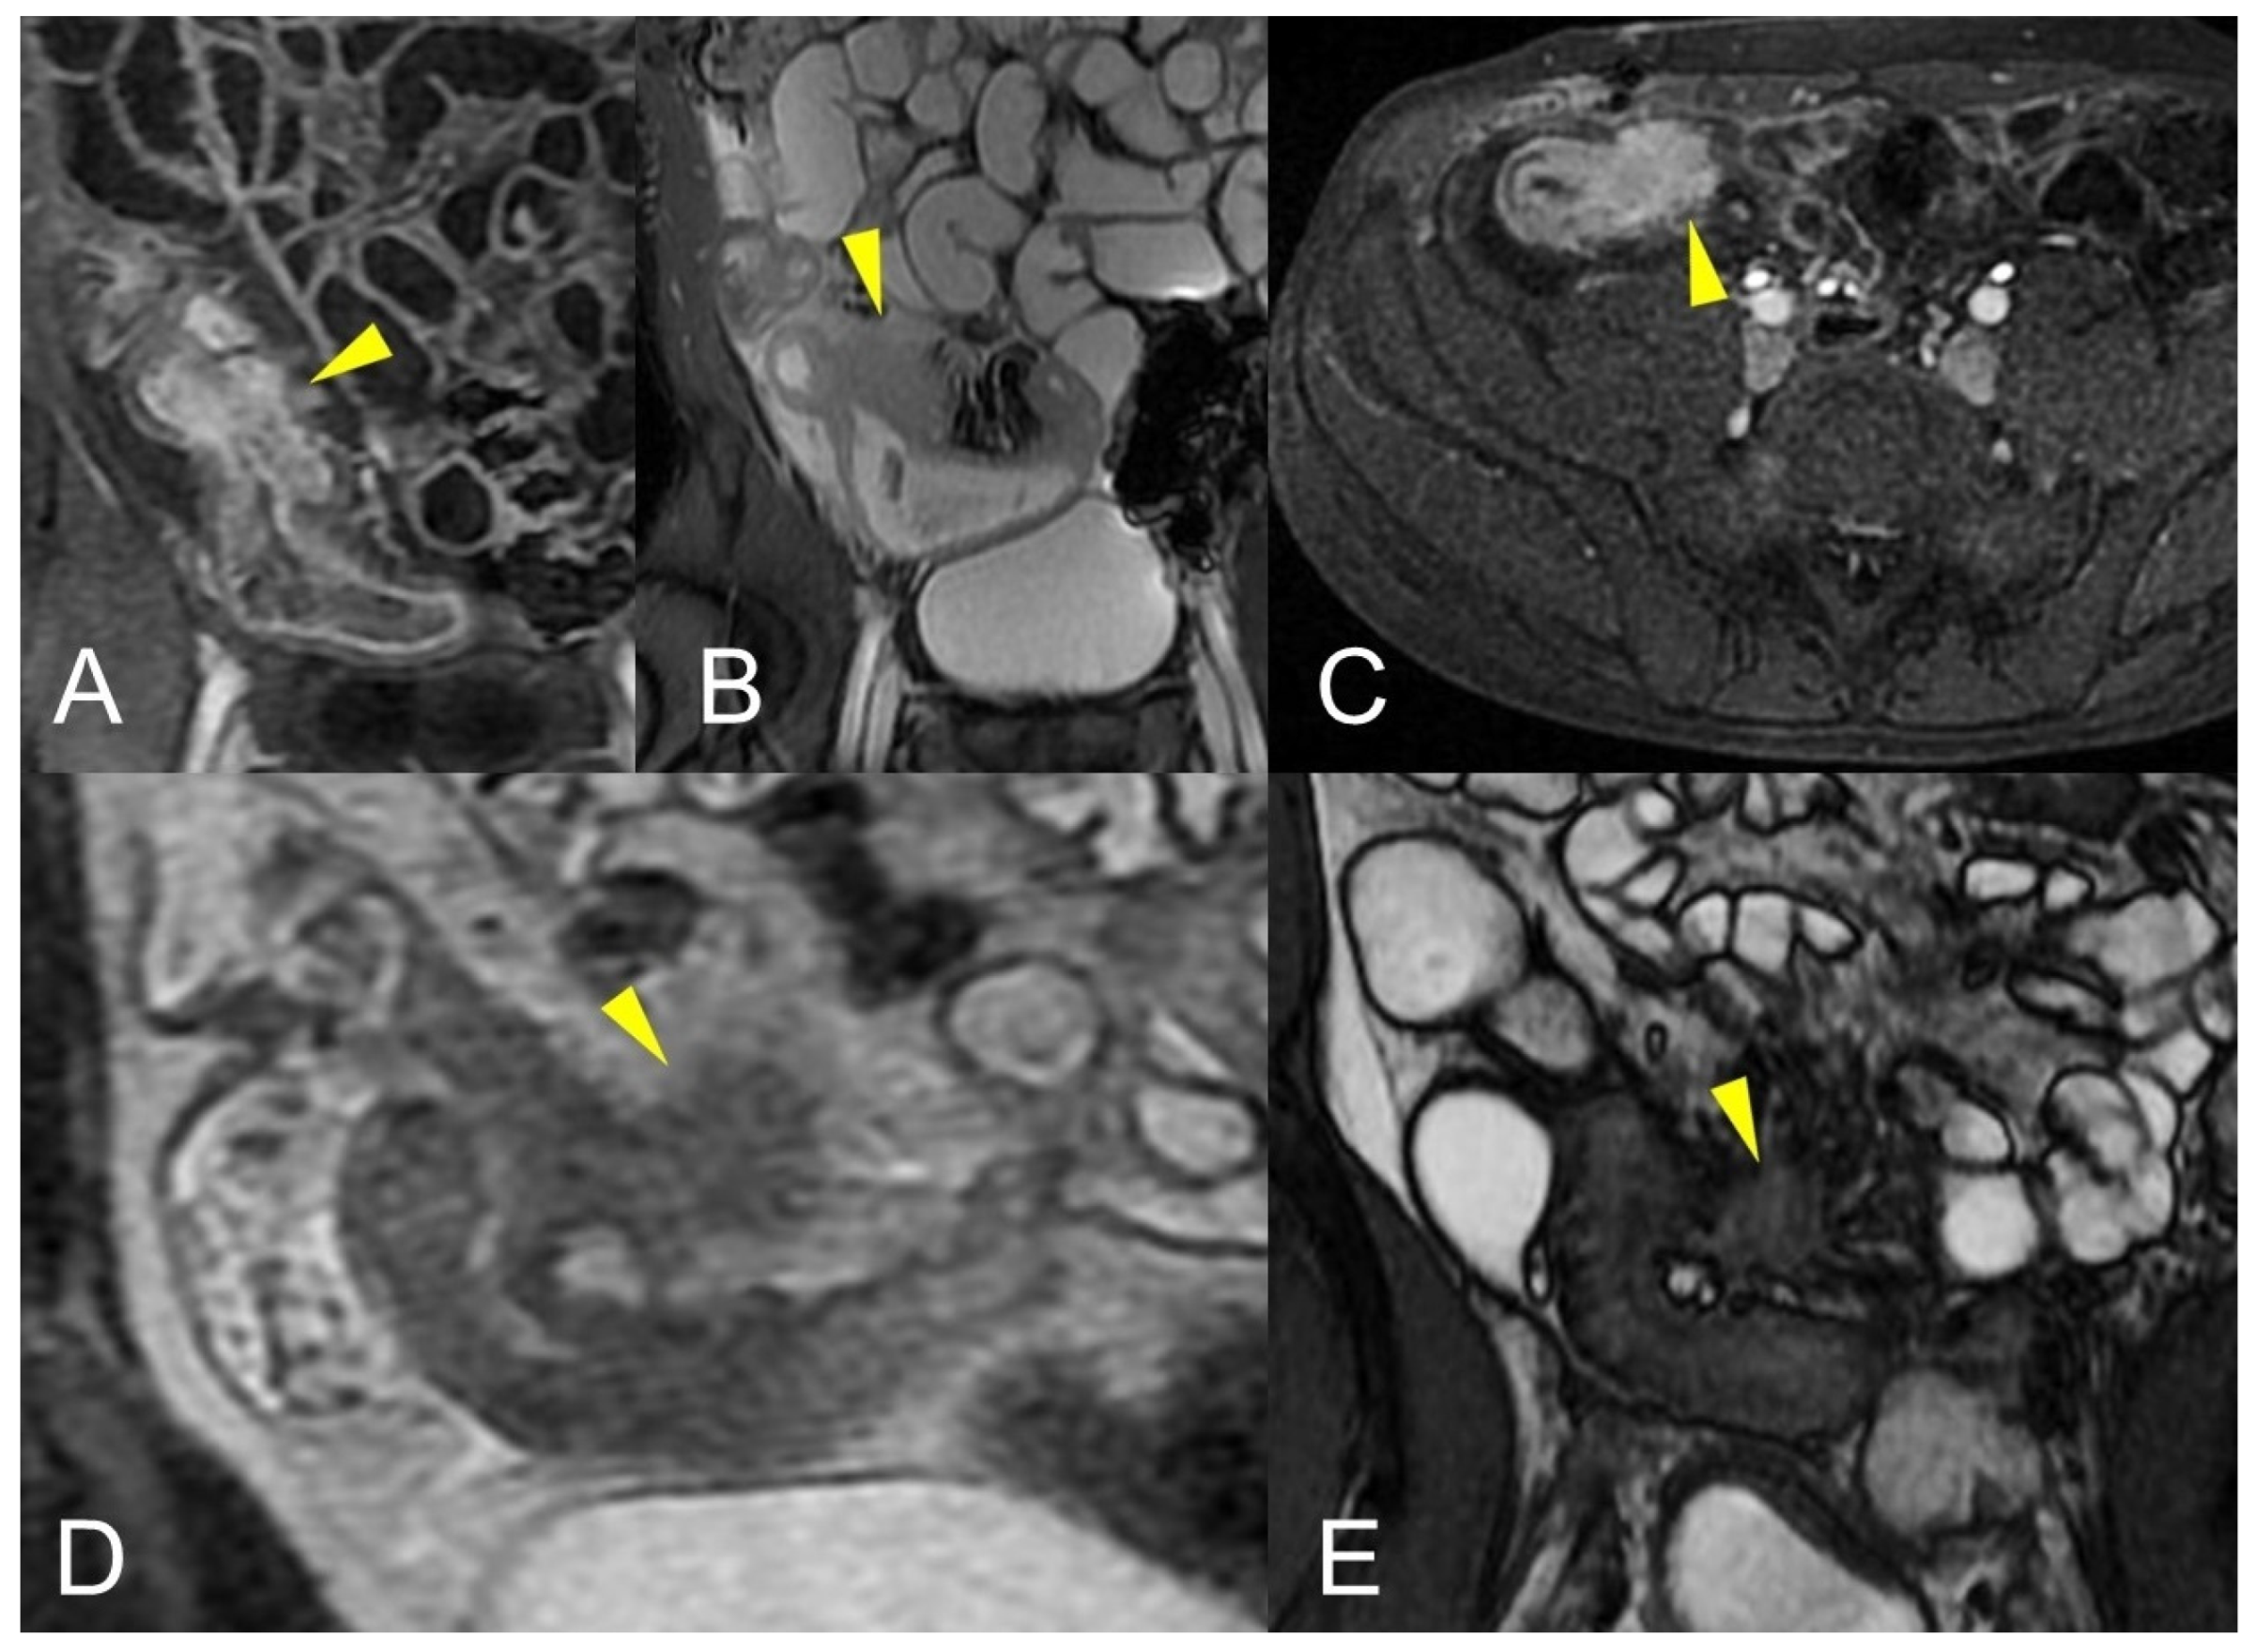

An abdominal phlegmon is an obsolete term that refers to an inflammatory mass that can develop in the setting of penetrating Crohn’s disease. The term phlegmon is ambiguous and relates to an ill-defined inflammatory dense mesenteric mass. It typically spreads without a well-defined wall and involves the mesentery and adjacent bowel with fistula or abscess as possible complication [12]. Inflammatory conglomerate is the accurate terminology to use in the radiological reports. On MRE images, it appears as a variable signal intensity mixed with fat, usually associated with signs of penetrating disease such as complex fistulas [5] (Figure 12, Figure 13 and Figure 14).

Figure 14.

Large climbing inflammatory conglomerate. A small abscess is evident in the center of the inflammatory conglomerate (yellow arrowheads in (A,D,E)). It shows marked enhancement (yellow arrowhead in (C)) and determines conspicuous retracting effects both on the mesentery (spiculate aspect in (D,E)), in which it develops, and on the adjacent loops. In this patient, the right distal pelvic ureter is also narrowed, (green arrowhead in (F)) with hydronephrosis (blue arrowhead in (F)). (A): coronal T2-weighted MRE image; (B,F): coronal fast imaging employing steady-state acquisition (FIESTA) image; (C): coronal contrast-enhanced fat-suppressed T1-weighted image; (D,E): axial contrast-enhanced fat-suppressed T1-weighted image.